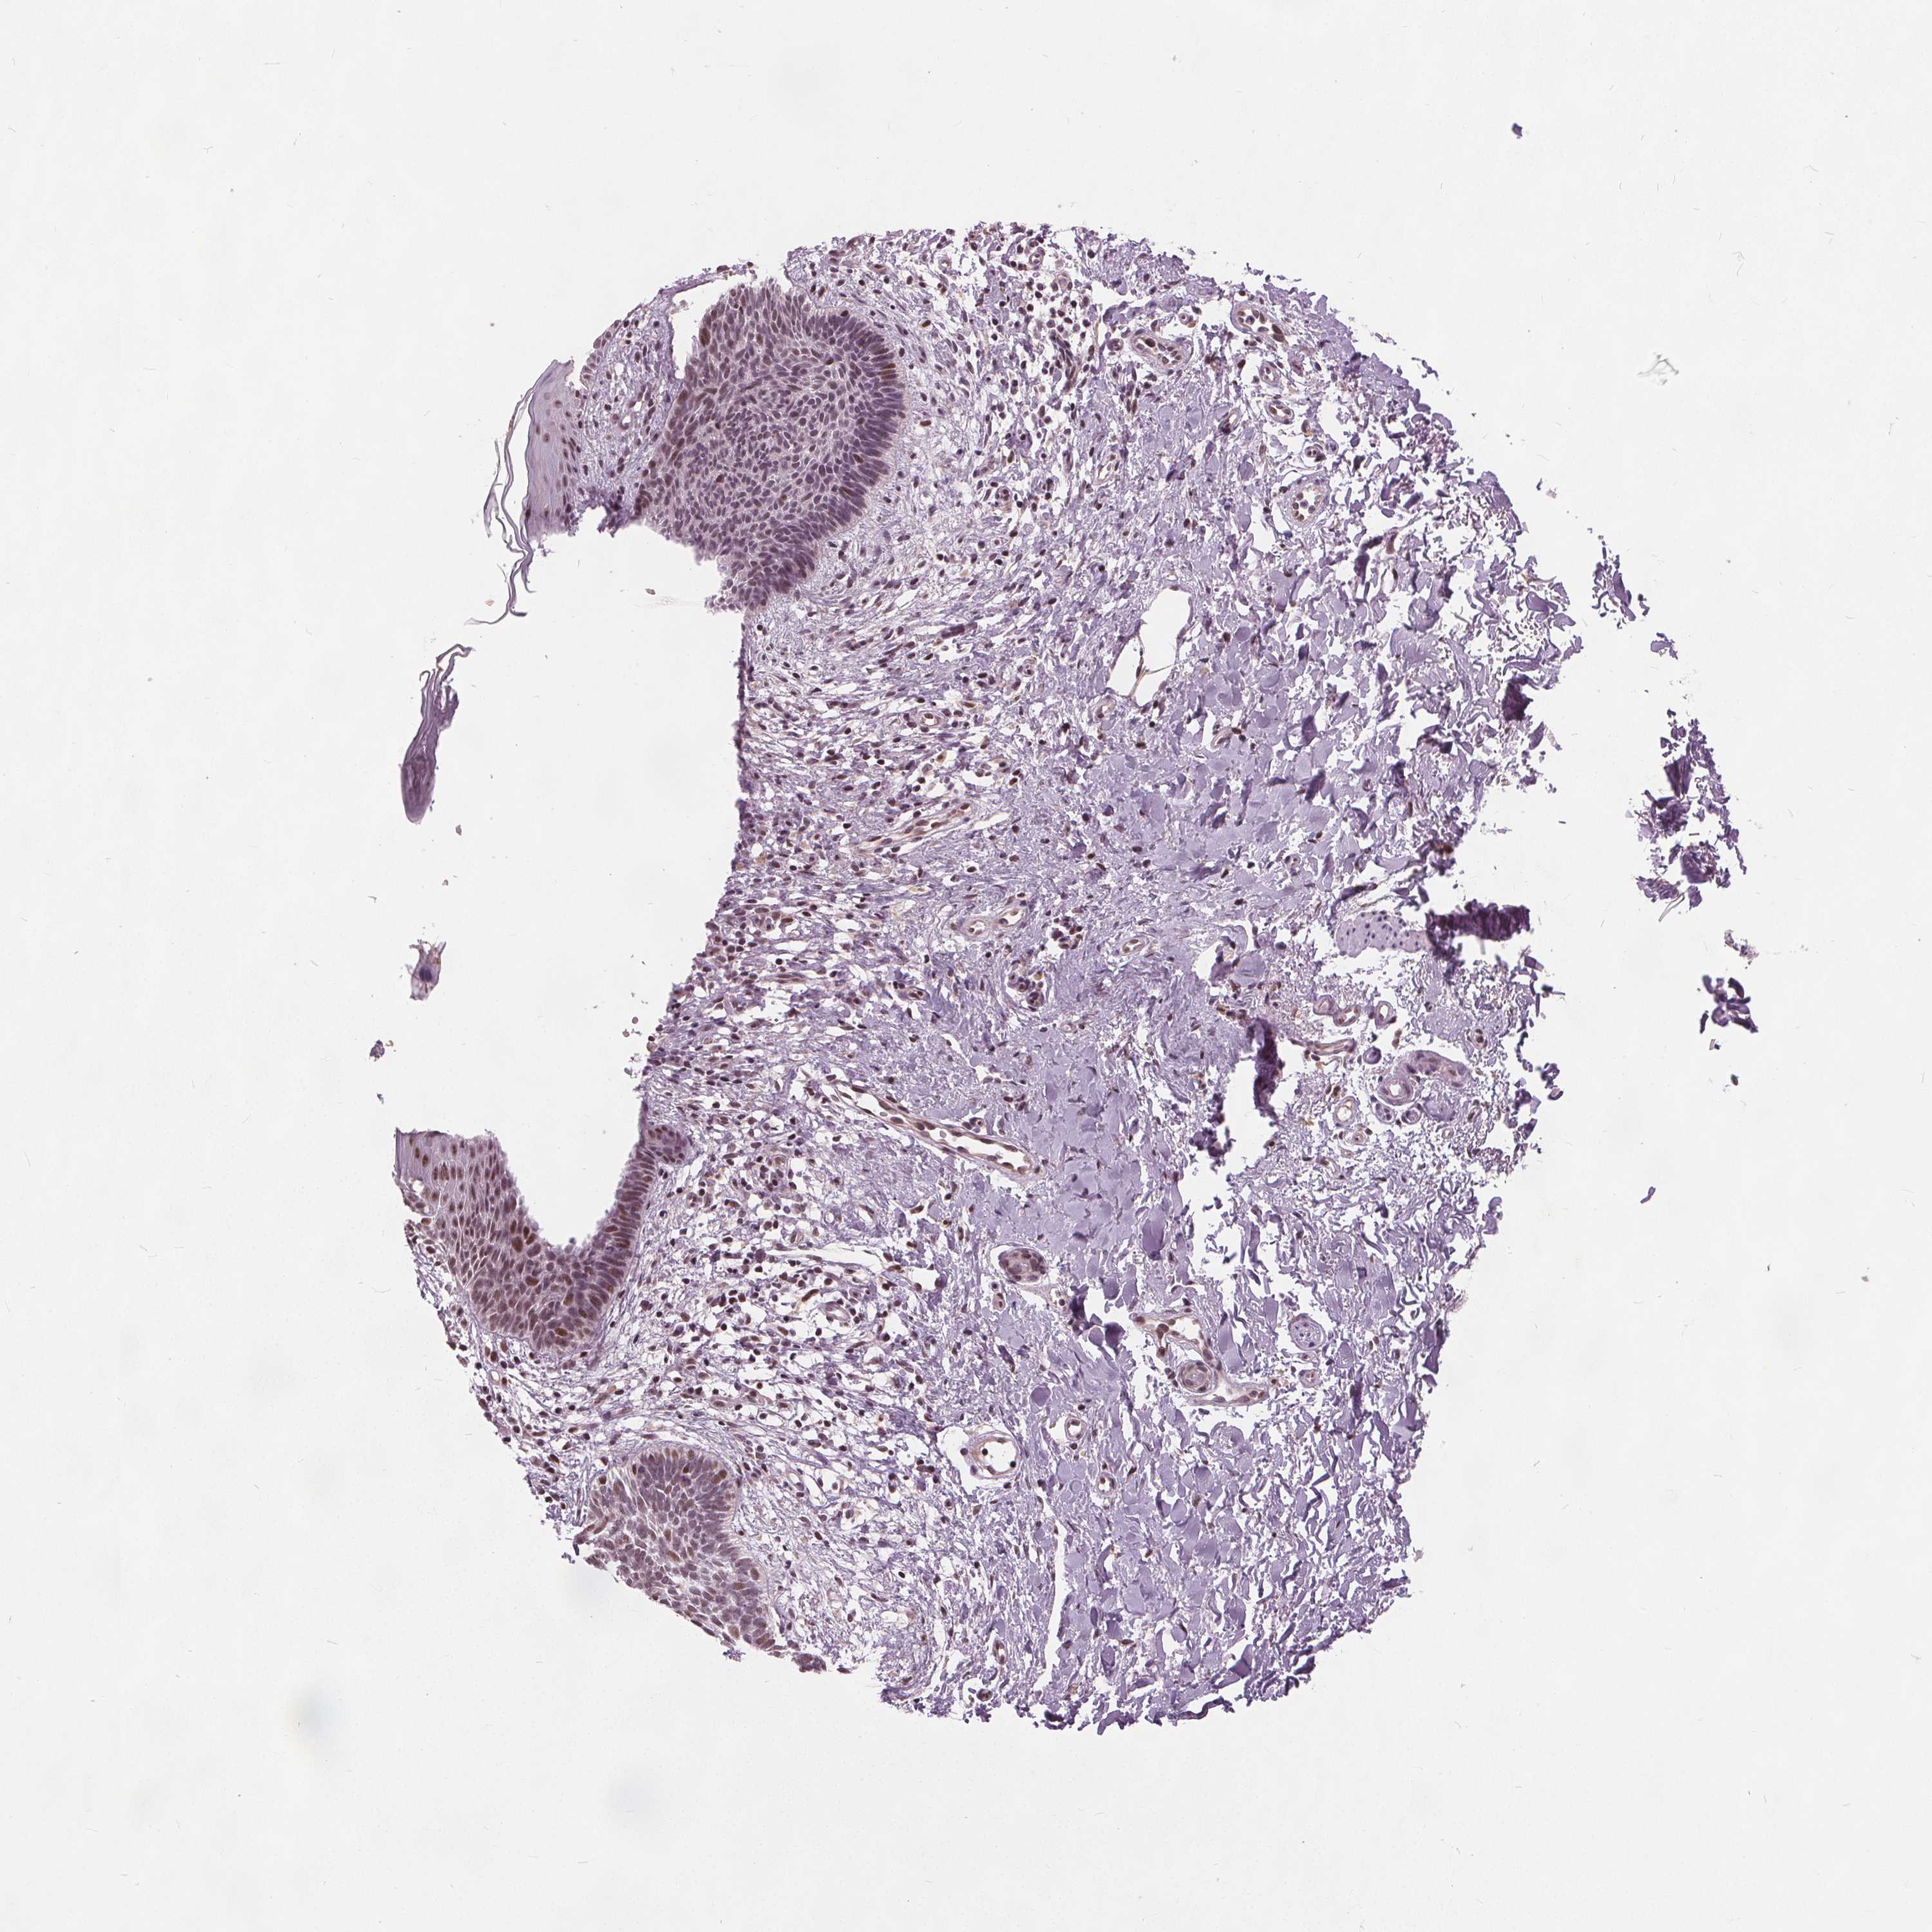

Basal cell and squamous cell cancer

SKIN CANCER - Protein expressioni

A mouse-over function shows sample information and annotation data. Click on an image to view it in a full screen mode. Samples can be filtered based on level of antibody staining by selecting one or several of the following categories: high, medium, low and not detected. The assay and annotation is described here.

Each image is clickable and will lead to virtual microscopy that enables deeper exploration of all samples and also displays staining intensity scores, fraction scores and subcellular localization as well as patient and tissue information for each sample.

Antibody HPA066832

Staining

High

Medium

Low

Not detected

Intensity

Strong

Moderate

Weak

Negative

Quantity

>75%

75%-25%

<25%

None

Location

Nuclear

Cytoplasmic/membranous

Cytoplasmic/membranous,nuclear

Basal cell carcinoma

Squamous cell carcinoma, NOS